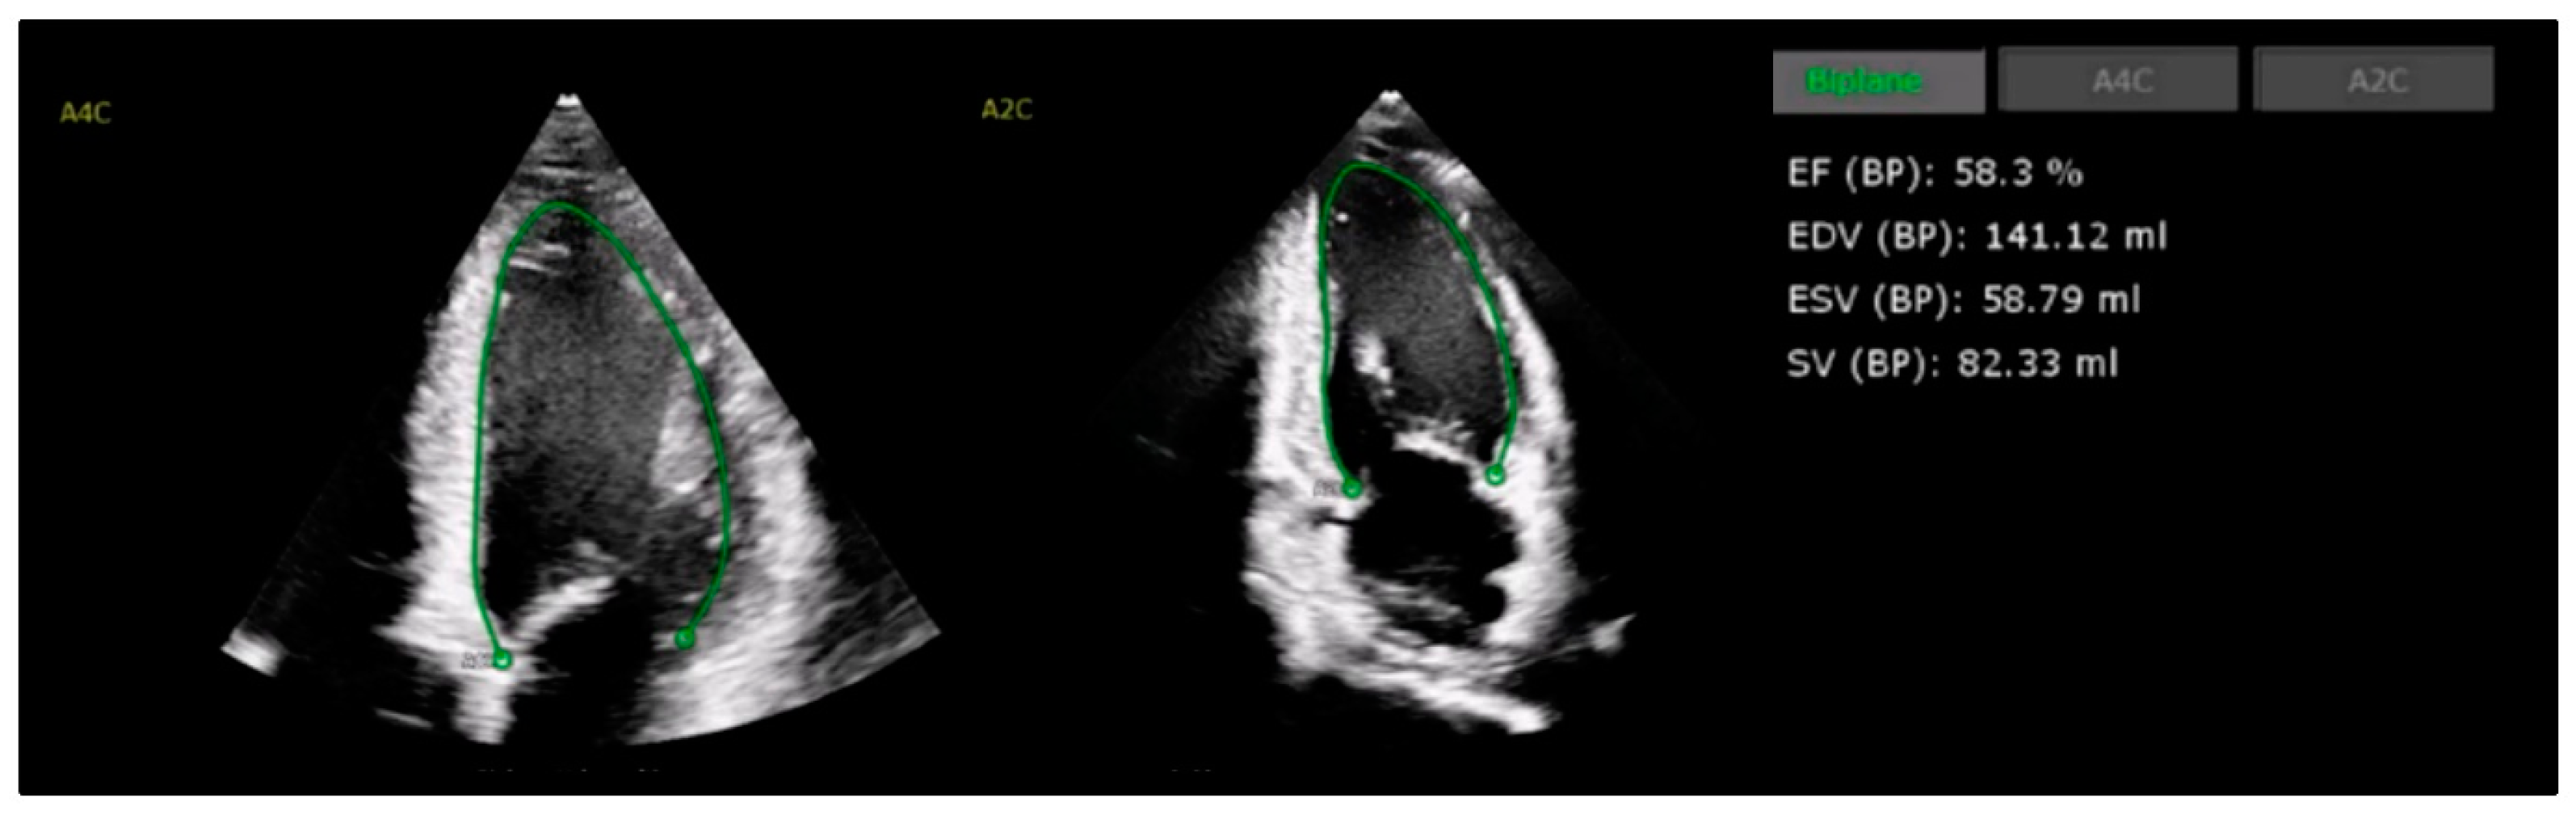

4.1. Left Ventricular Systolic Function

4.2. Global Longitudinal Strain